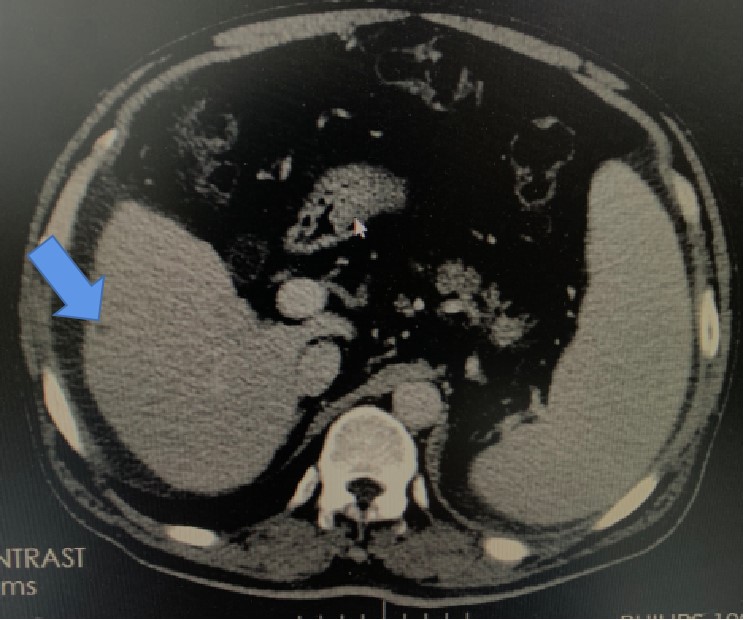

肝右叶小囊肿(箭头所指,小灶状,偏黑色部分)。